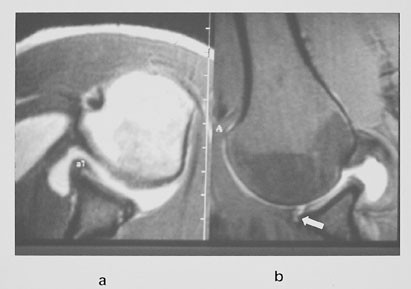

MR bekken og hofter

MR-undersøkelse av bekken og hofter blir ofte utført hos pasienter med hoftesmerter hvor konvensjonell røntgen er negativ. MR kan tidlig påvise en osteonekrose og stadieinndele den (fig 13). En klinisk tilstand kjent som beinmargsødem i forbigående osteoporose gir intraktable smerter (10). Dette er en tilstand hvor det er lokalisert osteoporose i caput/collum femoris assosiert med økt væske mellom trabeklene. Røntgenbilder er som oftest normale, spesielt tidlig i forløpet. MR vil vise generelt nedsatt signal på T1-vektet sekvens og betydelig økt signal på STIR-sekvens (fig 14). Tilstanden sees oftest hos middelaldrende menn. Den vedvarer i opptil seks måneder. Årsaken er ukjent.

Mistenkt collum femoris-fraktur er en hyppig årsak til sykehusinnleggelse. Pasientene er som oftest gamle og må få en rask og adekvat behandling. Konvensjonell røntgenundersøkelse kan være negativ eller vanskelig å bedømme. Tidligere utførte man planigrafi eller ventet noen dager for å ta nye bilder.

Vi har utført en MR-studie hos 27 pasienter med klinisk mistanke om collum femoris-fraktur der det var normalt eller usikkert funn ved konvensjonell røntgenundersøkelse (11). Det ble utført en koronal T1-vektet og en T2-STIR-sekvens, som til sammen tok under ti minutter. Vi fant 13 pasienter med collum femoris-fraktur eller pertrokantær fraktur, tre med bekkenringfraktur, en med acetabularfraktur, tre med muskelkontusjoner, to med beinmargsødem, to med artrose og tre normale. Vi utfører nå MR hos alle pasienter innen et døgn hvis vi er i tvil angående den konvensjonelle røntgenundersøkelsen (fig 15).